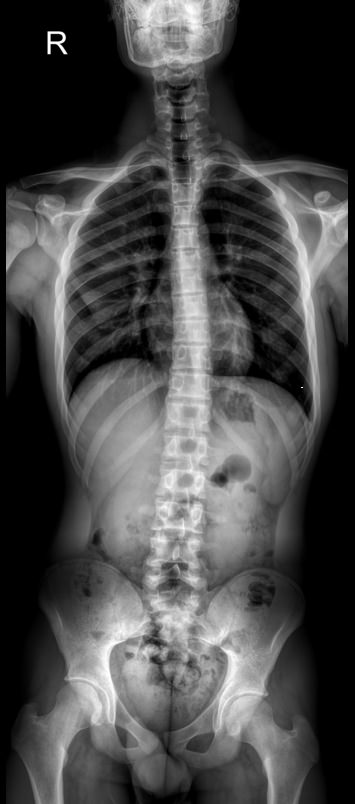

Назад Рентген позвоночника на кифосколиоз в прямой и боковой проекциях

При появлении признаков кифосколиоза или подозрении на него врач в качестве первичного обследования обычно назначает рентген. При этом рекомендован снимок всего позвоночного столба: как для выявления различных аномалий развития позвонков, так и для определения углов отклонения и, соответственно, степени заболевания. Для этого делают несколько обычных прицельных снимков и соединяют их в один с помощью компьютера. Несмотря на большую, казалось бы, дозу облучения, волноваться не стоит. Современное цифровое рентгеновское оборудование излучает настолько маленькую дозу, что даже при серии снимков трудно набрать допустимое для человеческого организма количество облучения.

Врач-рентгенолог  высчитывает углы возникшей деформации. Для определения угла кифоза на боковой рентгенограмме вычерчиваются линии, соединяющие нейтральные, то есть не измененные позвонки, с тем, что находится на самой вершине. Угол между ними и будет искомым. Угол сколиоза определяют по снимку в прямой проекции.

• Угол или углы сколиоза;

• Угол кифоза;

• Изменения шейного и поясничного лордозов: сглаживание или усиление;

• Врожденные аномалии, вызвавшие развитие кифоза;

• Остеопороз, склероз и другие изменения ткани тел позвонков;

• Наличие ротации позвонков;

• Уменьшение межпозвонковых промежутков, признаки дегенеративных процессов в них;

• Переломы, вывихи, новообразования, если они есть.

Для диагностики кифосколиоза необходимы 6 снимков:

• Шейного, грудного и пояснично-крестцового отделов в прямой проекции;

• Те же самые отделы в боковой проекции в состоянии максимального разгибания.